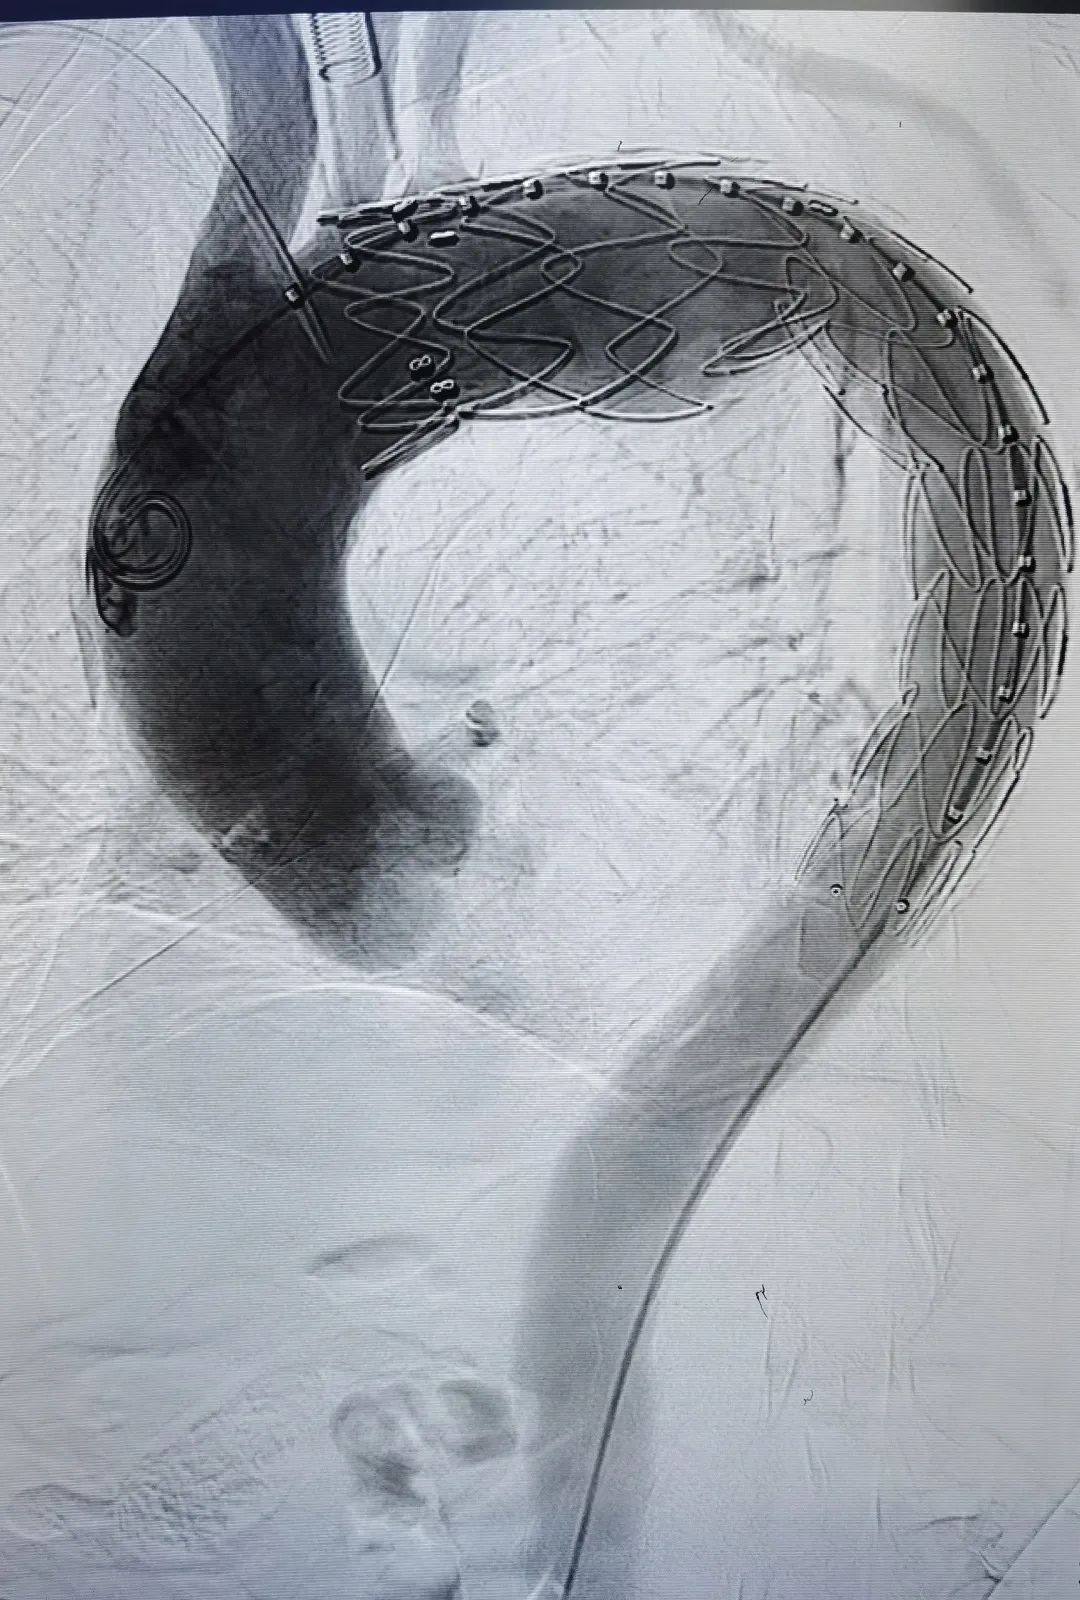

家属的积极态度让医生的顾虑少了很多,手术团队立即行动起来,全力以赴迎接挑战。考虑到老人年纪太大,病情十分危急,承受不了开放手术,伍源选择了微创的“主动脉腔内隔绝术”。

手术时,在患者大腿根部开一个3厘米的切口,从股动脉插入导丝,支架顺着导丝进入血管,到达病变区域,精确定位后释放支架,隔离膨出的瘤子。整个手术操作非常精细,无论是手术医生,还是麻醉师,都需具备丰富的临床经验,随时应对手术台上可能出现的变化。最终,手术团队密切配合,顺利隔离膨隆的主动脉瘤,将其与主动脉隔绝。这样一来,即使瘤子破了,也不会导致大出血。